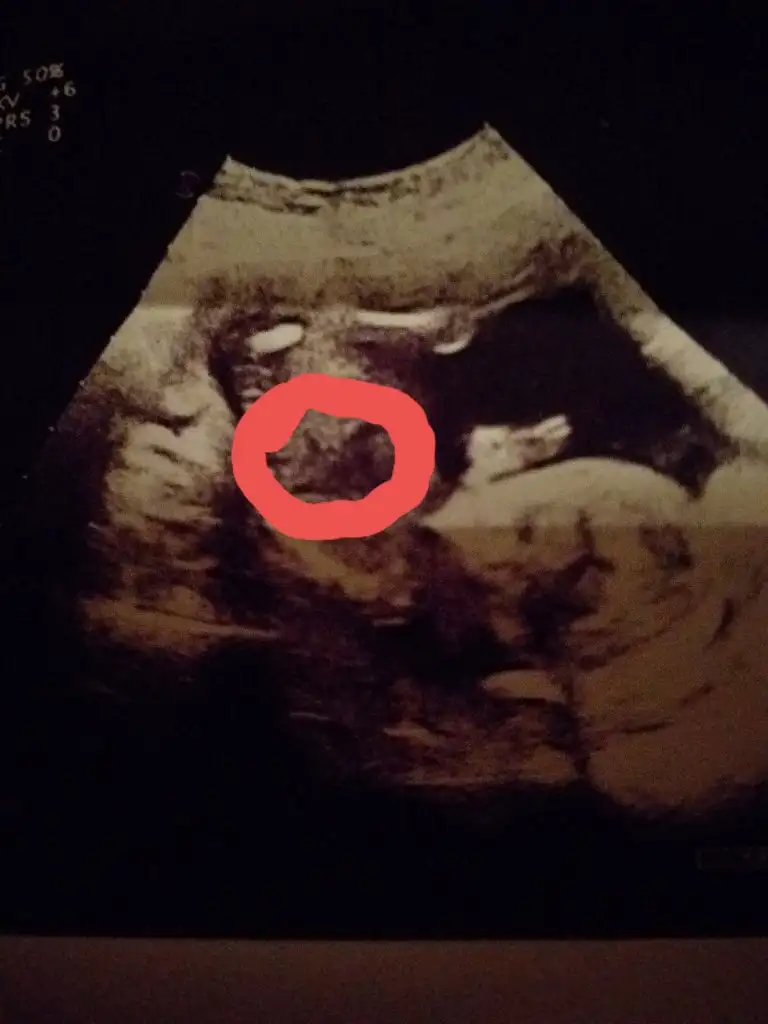

Yorum yapabilir misiniz erkek mi sizce

16 haftalik burda 13 haftalik net degildiKaç haftalık usg bu orada net birsey göremedim 11 yada 12 hafta usg olmalı

Net degil hayırlısı neyse o olsun sizin için

Bence kız bu bebiş

Ben Kıza benzettim

Erkek bebişarkadaşlar merhaba 12.hafta görüntüsü bebeğimin doktor erkek gibi konuştu ama net birşey demedi sizin tahmininiz nedir?Eki Görüntüle 2560931 Eki Görüntüle 2560931

teşekkürler bana da öyle geliyor bacak arası çıkıntı çok belirgin gibiErkek bebiş